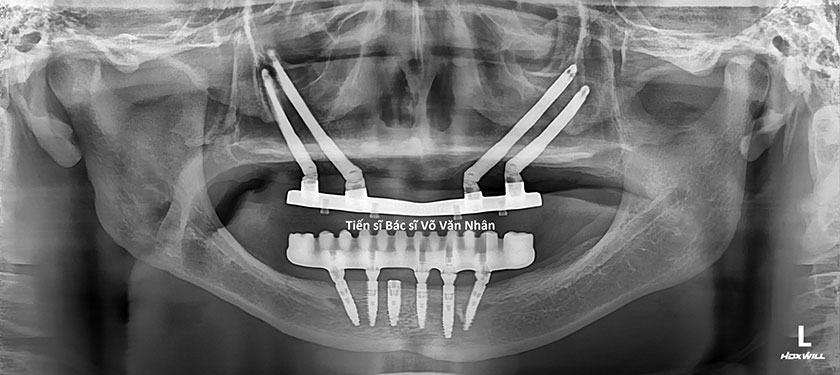

Phim XQ cấy ghép Implant của bệnh nhân không răng bẩm sinh

Sau khi khám và khảo sát trên phim X-quang, BS. Nhân cho biết đây là một trường hợp vô cùng đặc biệt, xương hàm trên của bệnh nhân tiêu sát đáy xoang hàm và xương hàm dưới tiêu lộ dây thần kinh.

Để phục hồi chỉ còn một giải pháp duy nhất là thực hiện đồng thời hai kỹ thuật: dời dây thần kinh, cấy ghép implant để phục hồi răng hàm dưới(*) và cấy ghép implant xương gò má để phục hồi răng hàm trên(*).